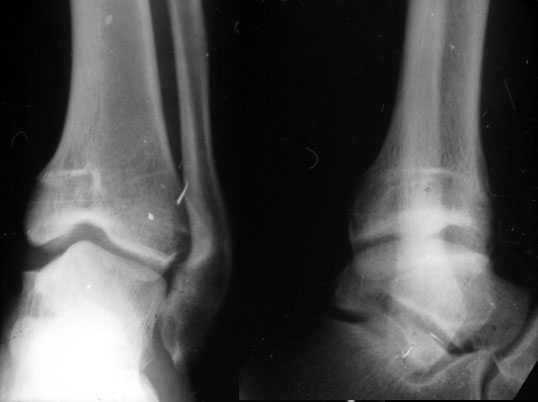

Скорее это перелом пилона 43В

представляю

> сегодняшние снимки. Главный вопрос : что делать?

Оперировать. Остеотомия, исправлять ось. Вопрос чем фиксировать? Зависит от того, чем владеете, что у вас есть в отделении, что может себе позволить пациент.

Согласен, тут деформация меньше, но все-таки заметная, почти 20 градусов. Я бы устранял ее как на приложенной картинке.

Перелом пилона сопровождается "компактированием метафиза" в дистальном отделе. Поэтому при фиксации переломов, после дистракции большеберцовой, очень важно провести замещение метафизарного "дефекта" костными или синтетическими заполнителями.

Без замещения дефектов из-за отсутствия опоры, переломы, со временем срастаясь, имеют тенденцию деформироватся в варус.

Медиальная подпорка "buttress technique" пластиной после пластики или хотя бы медиальная наружная фиксация более адекватны для удержания перелома, чем медиальные шурупы.